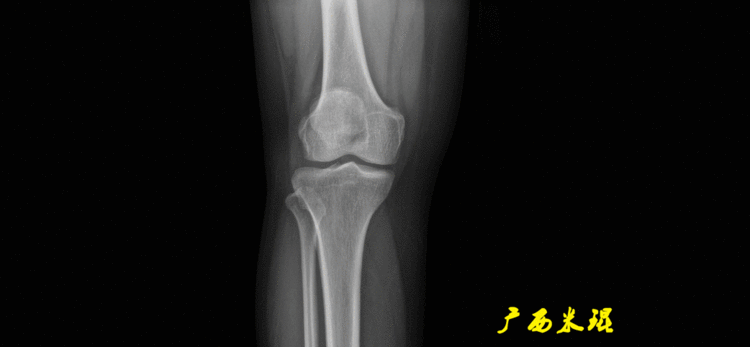

患者直立于摄影架上,后背贴近摄影架,双手自然下垂,膝关节尽量伸直,足部与双肩同宽,要求投照时双髌骨朝正前方,通常患者双足尖应平行向前即可。

提醒一下大家,拍摄过程中应避免下肢的外旋和内旋。如果有一侧肢体短缩时,投照应当用脚垫垫高短缩肢体,使骨盆保持水平,这样下肢短缩测量才精确。如果有肢体旋转畸形时,还是以髌骨朝前为标准,虽然此时双足可能不能保持平行。

无论如何,拍摄出来的下肢全长片必须包含髋关节中心、膝关节中心及踝关节中心,否则对临床是无用的。有了一张下肢的全长照片,我们需要确定下肢关节的中心点,通过中心点画出下肢的各种轴线,然后利用轴线与关节线的相交得出各种所需要的角度。